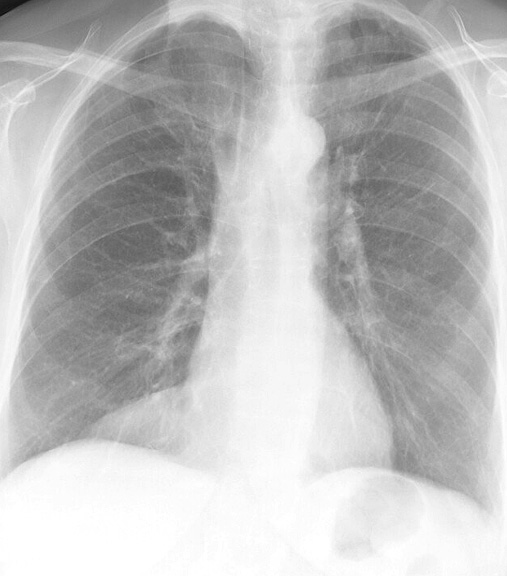

Fat Pad

Case 2a